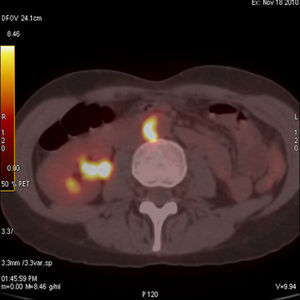

Case 2This case was a 74-year-old woman with pain and weakness of the shoulders and hips, with morning stiffness of more than 1h and elevated acute phase reactants. Suspecting polymyalgia rheumatica (PR) we administered 30mg/day of prednisone with initial improvement, but rapid recurrence of symptoms and deterioration in the laboratory tests, with a hemoglobin of 8mg/dl, CRP 19mg/dl and an ESR of 120mm in the first hour. The patient reported no headache, jaw claudication or tenderness on the temporal artery and peripheral pulses were normal. Suspecting a neoplasia we requested tumor markers, a thoracoabdominal CT, gastroscopy and colonoscopy, all with normal results; the study was completed, finally, with the performance of a PET-CT (Fig. 2) which evidenced a vasculitic process in the Ao, innominate, carotid and subclavian arteries. Given the strong suspicion of GCA we performed a temporal artery biops, which confirmed the diagnosis.